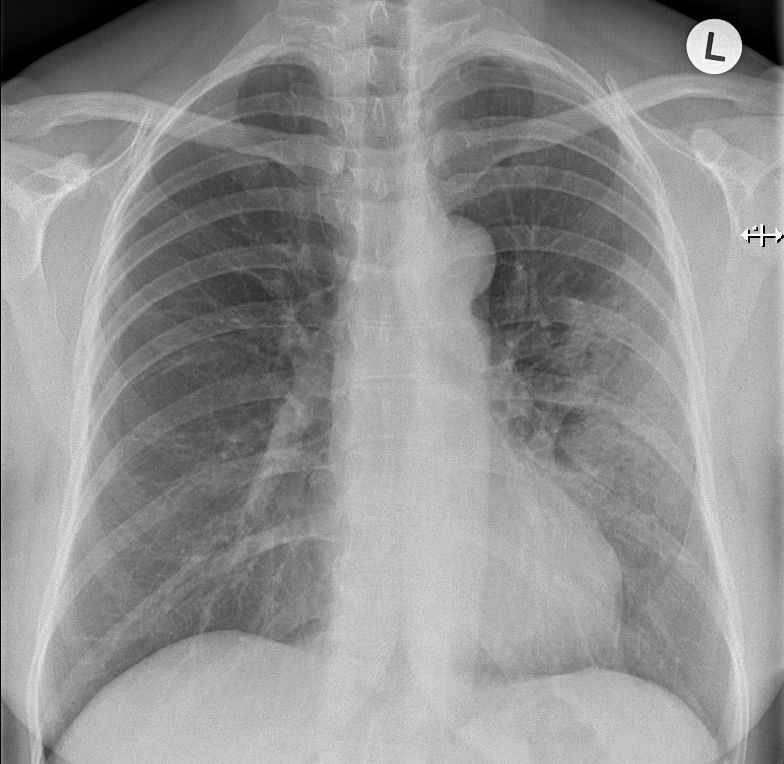

Pneumonitis 53-jährige Frau mit Mammakarzinom links. 3 Monate nach brusterhaltender Therapie und Bestrahlung der Brust wird die Patientin wegen einer Pneumonie ins Krankenhaus eingewiesen. Nach Gabe von Antibiotika zunächst nur geringe Besserung.

Das Thoraxbild zeigt ein Infiltrat im linken Mittelfeld.

Das CT zeigt eine Anschoppung direkt unter der bestrahlten Brust. Negatives Bronchogramm gut erkennbar.

Durch ein leichte Trichterbrust war ungewöhnlich viel Lungenparenchym in der Tangente bestrahlt.